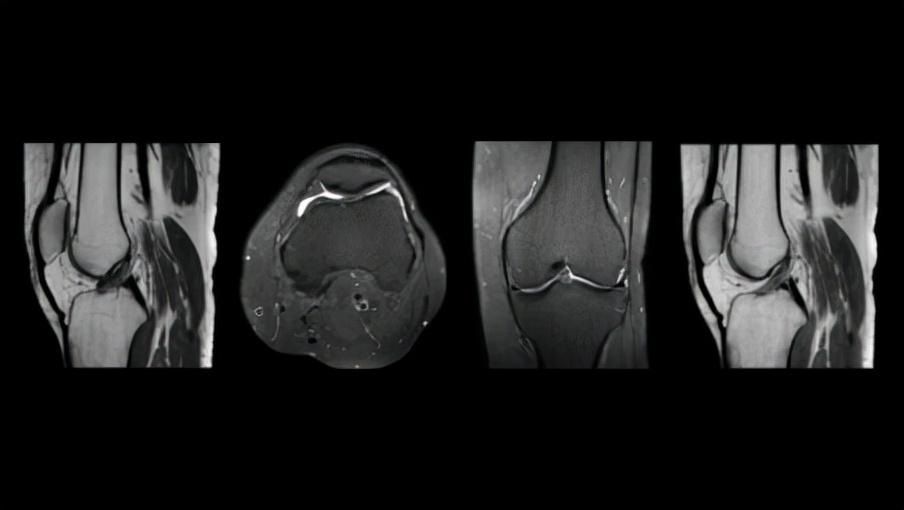

MR 5300大(55 厘米)视场提供了更大的解剖覆盖范围,同时其强大的AI驱动扫描方法和易于定位的超轻量dStream Breeze线圈相结合产生优质的图像质量,尤其是在对具有挑战性的解剖结构,如脊椎、腹部进行成像时比。通过简化、自动化捕获高质量图像所涉及的复杂临床和操作任务,MR 5300提高了放射科输出的一致性和生产力,有助于提高患者满意度和转诊率,其无氦操作使其适用于门诊和专门的放射科。